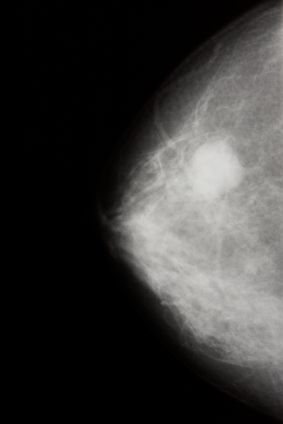

ДИАГНОСТИКА

Для постановки диагноза врач изучает анамнез болезни, жалобы больной, клиническую картину заболевания, проводит физикальный осмотр, лабораторные и инструментальные исследования: маммографию, узи молочной железы, пункционную биопсию опухоли, для исключения метастазов в другие органы - радиоизотопное исследование костей (сцинтиграфию), УЗИ органов брюшной полости, рентгенографию грудной клетки, клинический и биохимический анализы крови и др.